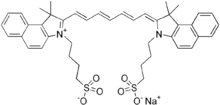

| Indocyanine Green |  Indocyanine Green |